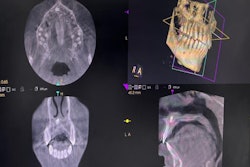

The use of cone-beam computed tomography (CBCT) in younger pediatric patients has risen every year since 2017, indicating increased awareness about the uses of the imaging modality. The study was published on January 19 in the International Journal of Paediatric Dentistry.

Though CBCT is used widely with pediatric dental patients, using the imaging modality appropriately is critical, since children are more vulnerable to ionizing radiation than adults. Ionizing radiation exposure can cause permanent DNA damage and mutations that cause cancer. Since tissue cells in children divide faster than those in adults, children have up to a 10 times greater risk of ionizing radiation, according to the study.

To explore the use of CBCT in pediatric dentistry, the authors evaluated 334 CBCT scans taken at different times and for distinctive reasons in 319 patients.